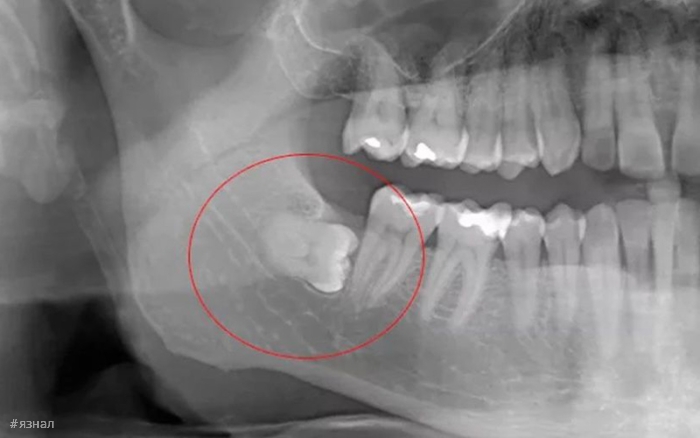

- Импакция: Зуб может быть частично или полностью заблокирован в тканях десны или кости. Это состояние вызывает боль, отеки и инфекции.

- Неправильное Положение: Если зубы мудрости прорезаются под углом, это может повлиять на соседние зубы, вызывая скученность или повреждение других зубов.

Регулярные посещения стоматолога помогут выявить потенциальные проблемы, связанные с зубами мудрости, даже до их появления. Стоматологи используют рентгенологические исследования для наблюдения за состоянием зубов мудрости и окружающих тканей.